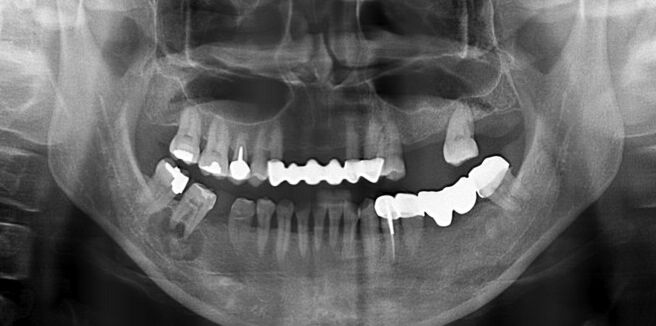

66.17歲男孩因上顎右側有一個無疼痛的腫脹而來求診,經X光檢查(如附圖)發現一個放射線不透過性影像如 箭頭所示之區域,根尖片可見到此病變與周圍界線不清楚,此病患最可能罹患下列何種疾病?

B)通常雙側、多處發生,可能會吃穿mucosa露出cemento-like的物質,PANO 初期看起來有點像periapical cyst後期RL的病灶中會包著RO(跟periapical cemento-osseous dysplasia一樣),不會造成bony expansion

D)好發於中年女性下顎後牙區,界限明確,中間出現鈣化組織(unilocular mixed RO/RL),可能會造成bony expansion